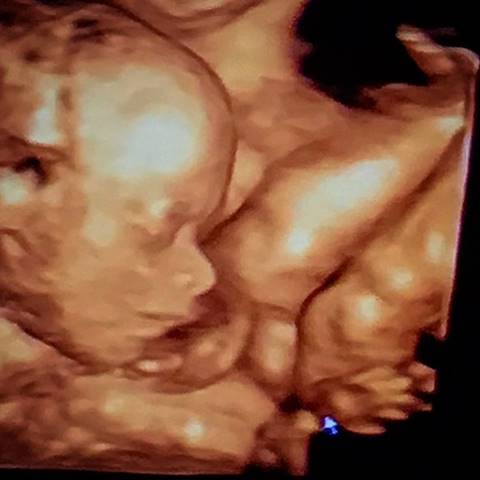

เติ้ล ตะวัน ได้ฤกษ์เป็นคุณพ่อมือใหม่ หลังภรรยาสาว กระแต คลอดลูกสาวคนแรก น่ารักน่าชังมิใช่น้อย

ขอแสดงความยินดีกับครอบครัว จารุจินดา ด้วยนะคะ ที่ในวันนี้ (22 พฤศจิกายน 2560) หนุ่มเติ้ล ตะวัน ก็ได้เผยโฉมสมาชิกคนใหม่ของบ้านเป็นที่เรียบร้อยแล้ว

เห็นน้องน่ารักแบบนี้ คุณพ่อคงชื่นใจ ไว้หนวดรอเลยใช่ไหมล่ะ อิอิ